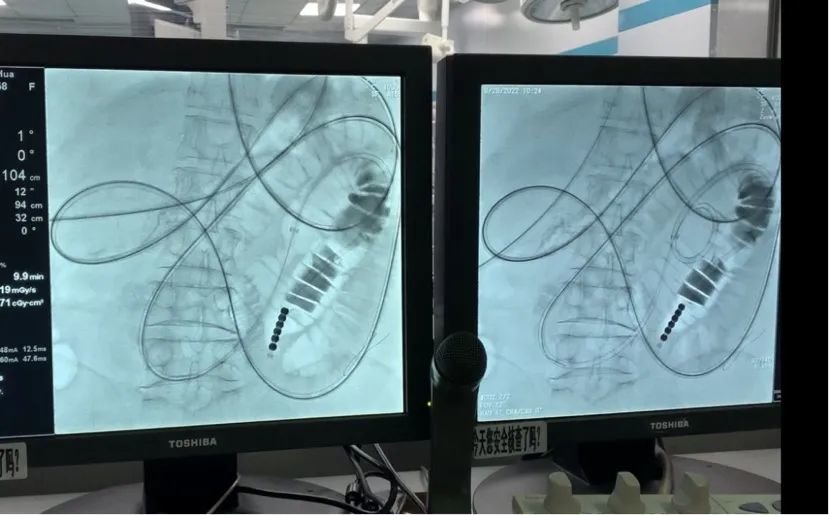

详细了解病情后,陈玉堂、刘爱华两位医生迅速带领团队做好术前准备。手术中,医护人员默契协作,将3米长的减压管绕过肠腔多个拐点,精准放至小肠梗阻部位,达到最佳减压效果。30分钟后手术结束,金女士症状明显好转。2天后,金女士恢复通气,6天后拔管进食。“解除病痛折磨后,我自己都觉得好像重生了。”金女士笑容满面地再三表示感谢。目前,金女士已经顺利完成新一期化疗,向医护人员们告别后出院回家。

“目前,临床上绝大多数的肠梗阻病例都可以通过介入的方法进行治疗,肠管再通率可以达到90%以上,能短期内恢复饮食。这种治疗方法不用开腹手术,创伤小、见效快、成功率高。”陈玉堂介绍,该科室在原有的肠梗阻治疗规范基础上,做了许多原创性、开创性工作,解决了一些过去临床难以解决的肠梗阻问题,治疗水平居于国内领先地位。